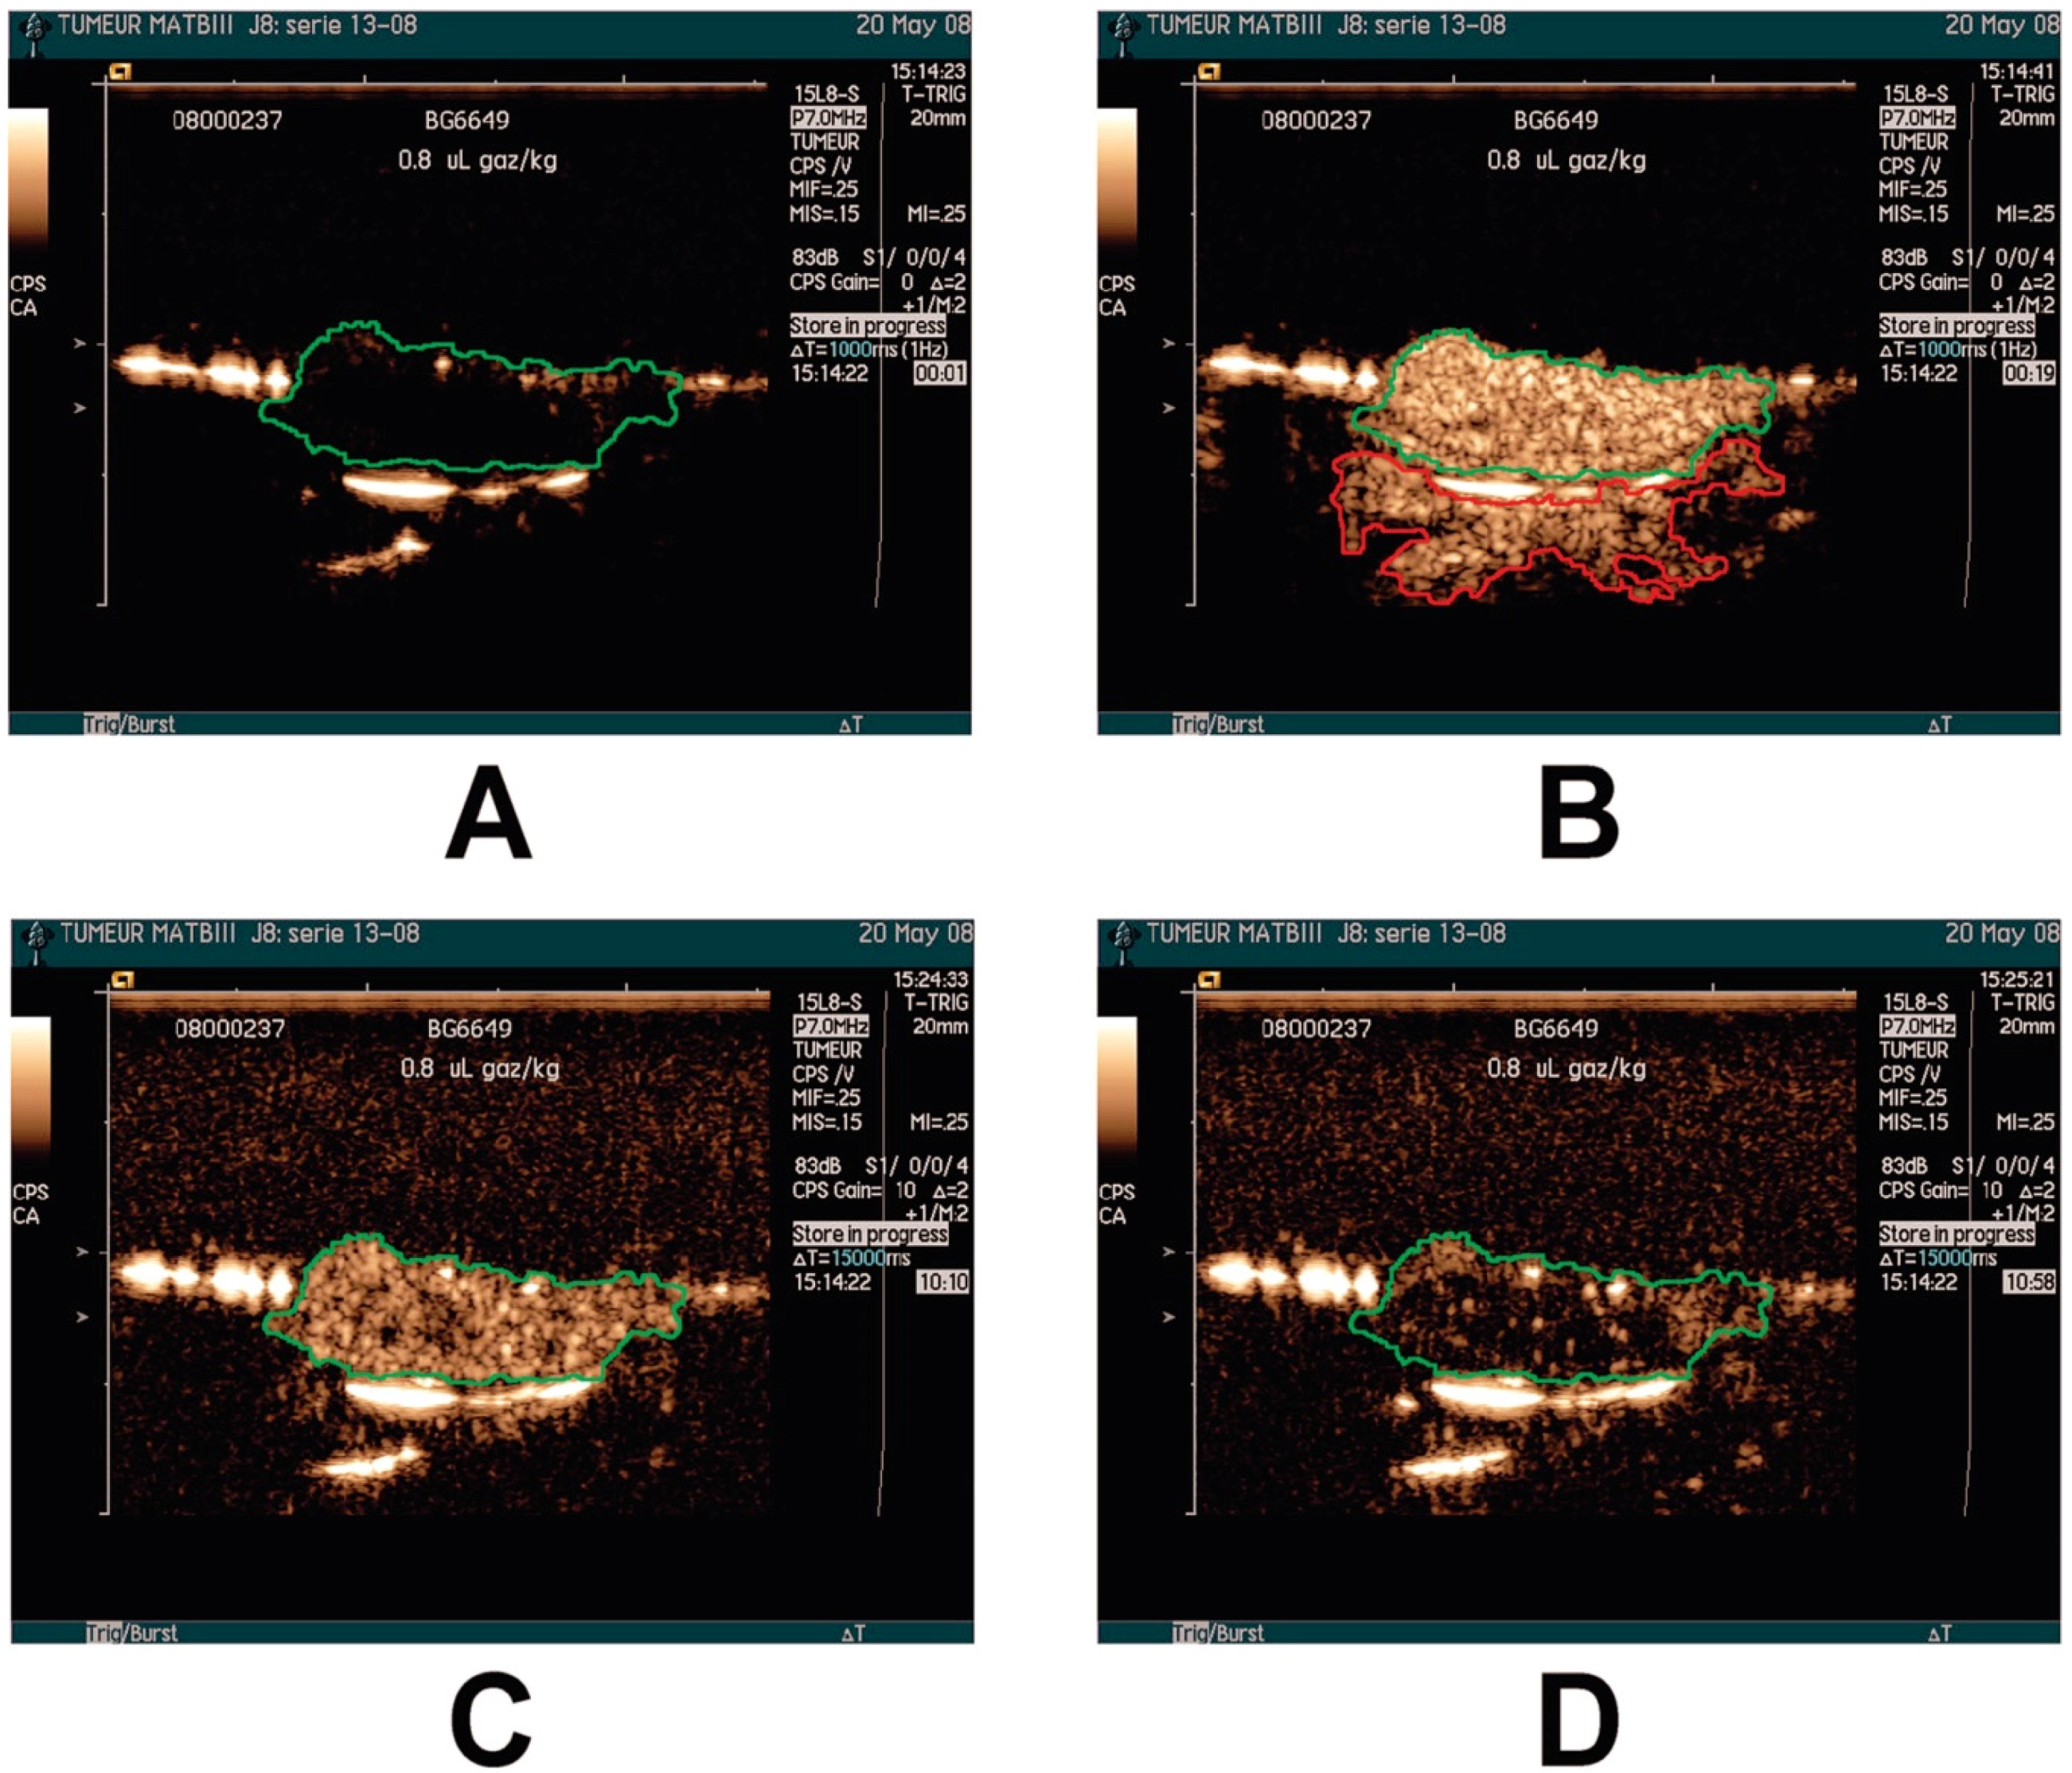

2.1. Tumor Detection